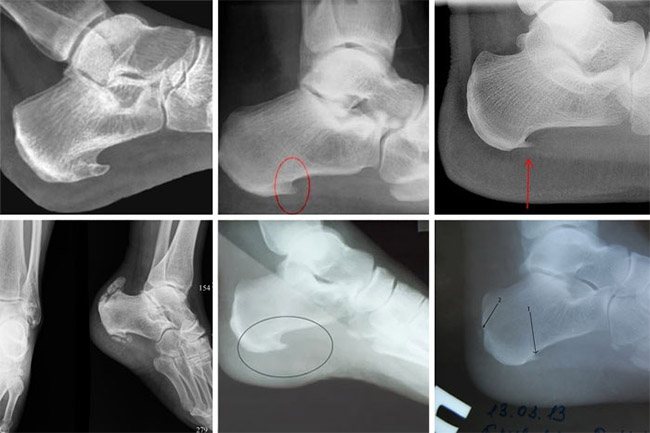

Сканирование пятки при наличии шипа проходит в следующих проекциях:

- Со стороны стопы

- Под различными углами – косо.

- Переднезадний снимок – говорит о работе костей стопы.

- С боку чтобы изучить рабочие характеристики суставов.

Когда обнаруживается на пятке шип, доктор описывает снимок – как расположен вырост, какая у него длина.

Шпоры в зоне пятки — это наросты на поверхности таранной кости, нередко в области задней или нижней плоскости бугра. Образования разрастаются по причине повреждения ступни, заболеваний суставов, неверно подобранной обуви, нагрузок физического характера.

Рентгенологические признаки шпоры

Признак пяточной шпоры – костные образования, располагаемые на плоскости кости, зачастую в месте бугра. Шпора на изображении представлена в качестве нароста на плоскости бугра — как шип, крючок, длина которого до 1 см. Диагноз пяточная шпора ведет к формированию мозолей, появляются кровоподтеки.